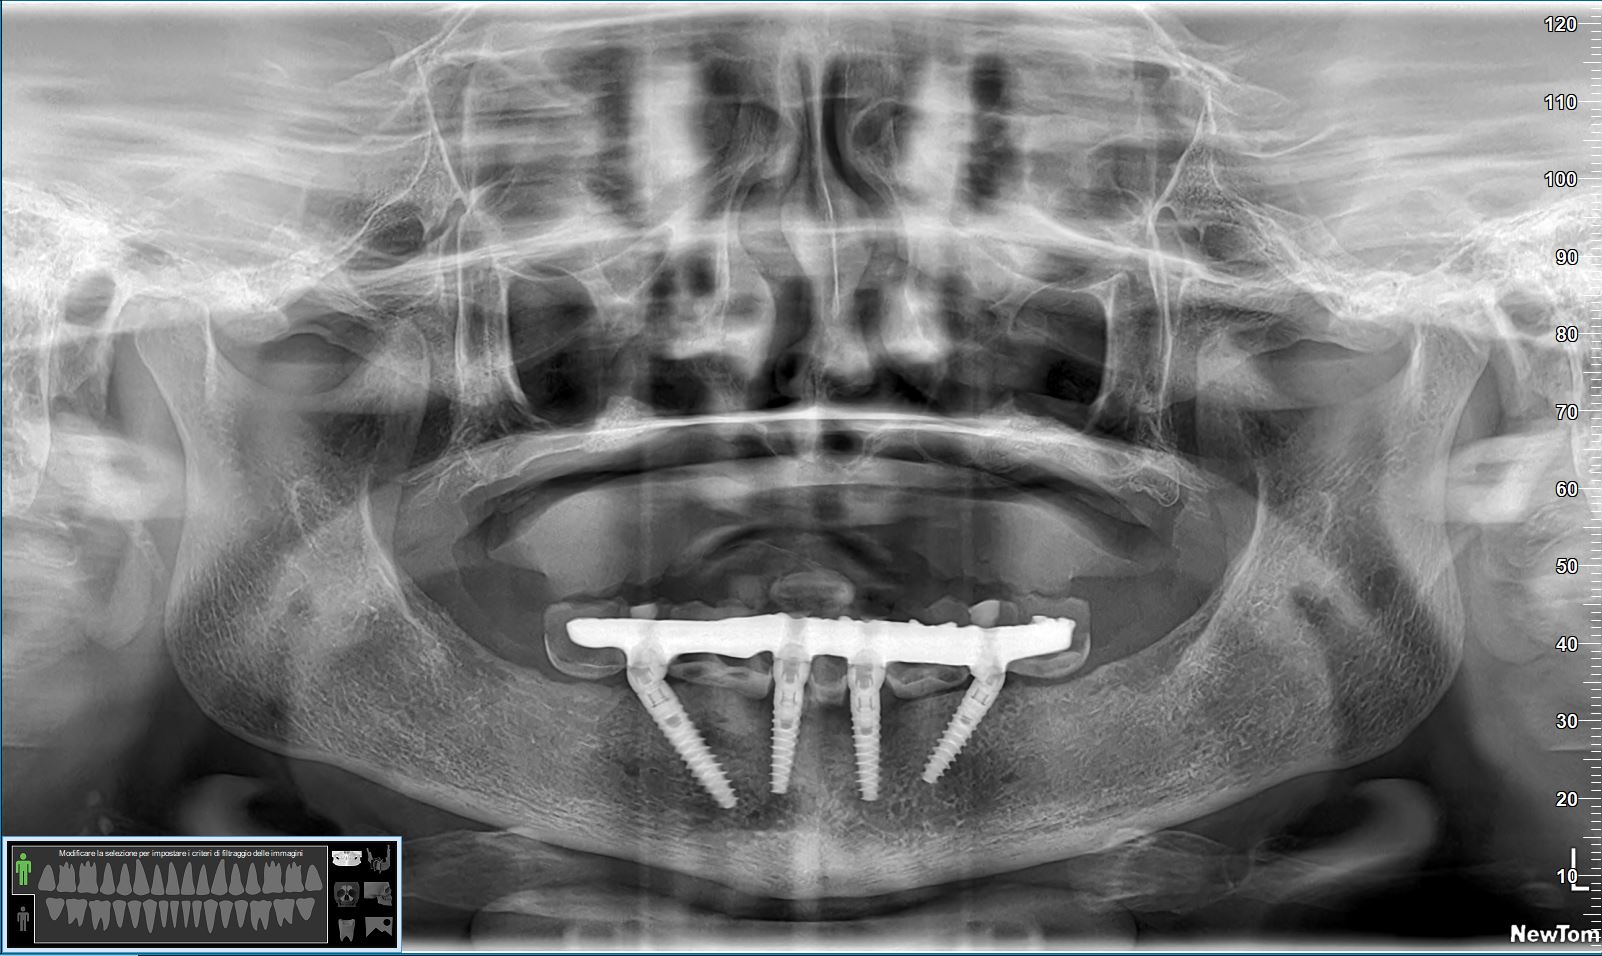

La paziente era stata trattata circa quattro anni fa presso un centro low cost del centro Italia, e quello che è successo a livello chirurgico è abbastanza chiaro: l’inconsapevole “chirurgo” aveva posizionato gli impianti in osso alveolare nella vana speranza che questo si preservasse nel tempo.

Stupidaggine, tra l’altro, che sta tornando in grande voga negli ultimi anni e che, come già avvenuto vent’anni fa, si riverserà sulle teste di chi la propina con una marea di fallimenti come quello che vedi qui.

Come si può osservare dal video, gli impianti non sono in perimplantite: semplicemente, l’osso si è riassorbito attorno lasciandoli fuori.

– E… non sarebbe stato più semplice lisciare le spire degli impianti posteriori (vedrai dal video che hanno la parete vestibolare totalmente fuori dall’osso)?